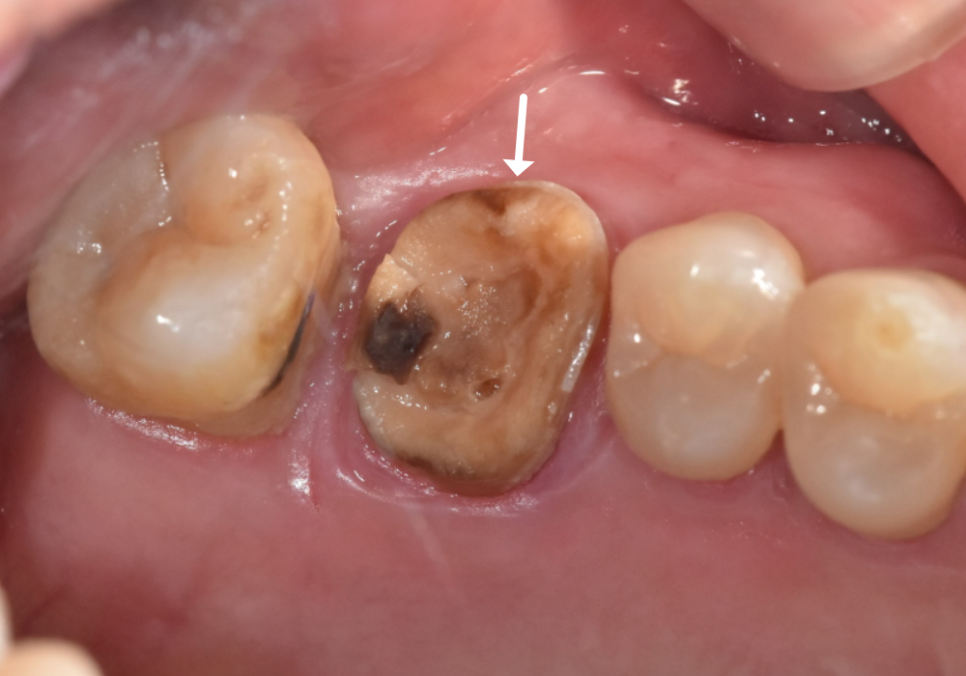

이번엔 반대쪽인

왼쪽 아래 어금니인 금니가

'툭' 하고 빠지신 건데요.

지난번 발치의 아픈 기억 때문인지,

"이번에도 뽑아야 하나요...?"

하며 걱정이 태산 같으신 모습이었습니다.

조심스럽게 빠진 자리를 살펴보니,

역시나 치아 내부에

까맣게 충치가 진행되어 있었죠.

250822

하지만..

엑스레이와 구강 상태를 꼼꼼히 확인해 보니,

이번 치아는 다행히

발치 없이 충분히 살려서 쓸 수 있는 상태였습니다.

이번 케이스가 지난번과 달랐던 결정적인 차이,

바로 금니 표면의 '구멍' 유무였습니다.